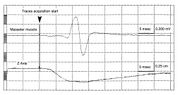

| 22:58, 15 July 2024 | Siro e jaw jerk 2.jpg (file) |  |

736 KB | Gianni | 2 | |

| 22:58, 15 July 2024 | Sirignathograph e jaw jerk 1.jpg (file) |  |

707 KB | Gianni | 2 | |